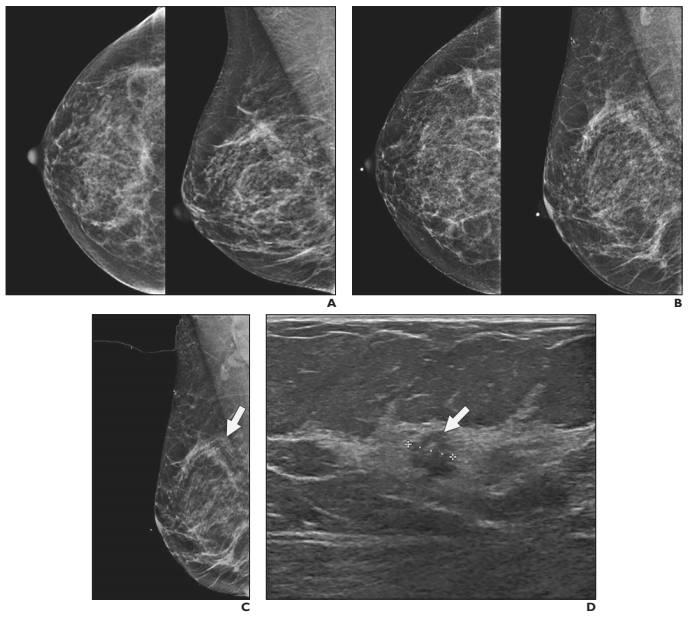

Imaging findings

Mammograms for breast pain in 78% of patients.

94% of which were diagnostic mammograms

A mammographic finding in the area of breast pain was seen in four of 625 mammograms.

Stereotactic biopsy was performed for two pa-

tients because of incidental findings; for both

patients, the findings were benign.